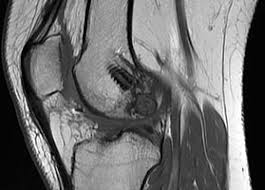

Ein kreuzbandriss (vorderes kreuzband) ist die häufigste bandverletzung des kniegelenkes, das hintere kreuzband reißt selten. Aber auch das hintere kreuzband kann reißen. Welche therapieoptionen im einzelfall infrage kommen, hängt unter anderem auch davon ab, ob zum beispiel ein „frischer oder ein „alter kreuzbandriss vorliegen und ob das vordere oder das hintere kreuzband betroffen ist. Wann wieder sport nach einem kreuzbandriss? Wann kannst du nach einer kreuzband op wieder laufen gehen? Unter bestimmten voraussetzungen kann eine kreuzbandruptur aber auch konservativ (ohne operation) behandelt werden. Eine falsche bewegung, das knie ist verdreht und sie fürchten einen kreuzbandriss.verletzungen des vorderen kreuzbandes (vkb) kommen tatsächlich häufig vor und werden oft bagatellisiert, vor allem, wenn keine starken beschwerden auftreten. Ein kreuzbandriss ist eine der häufigsten verletzungen des kniegelenkes. Das auto gehört für viele zum alltag und oftmals auch zum arbeitsleben. Da ich aber sehr gern jogge und zudem ein recht talentierter fussballschiedsrichter mit chancen auf erfolg auf dem gebiet habe, würde. Von einem kreuzbandriss sind häufig leistungssportler betroffen. Ich hab gelesen, dass ballspiele wie fussball, basketball etc erst nach 6 monaten wieder betrieben werden sollten. Beachten sie ihren versicherungsschutz, der häufig erst vier wochen nach der operationen greift.